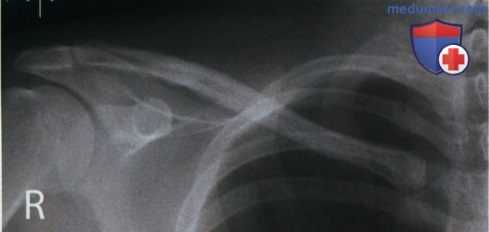

Рекомендации по анализу изображений (рис. 1 и 2):

РИСУНОК 1 Рентгенограмма акромиально-ключичного сустава в ПЗ проекции (без нагрузки): правильная укладка. РИСУНОК 2 Рентгенограмма акромиально-ключичного сустава в ПЗ проекции (с нагрузкой): правильна укладка.

• Латеральный отдел ключицы направлен горизонтально

• Между латеральным концом ключицы и верхушкой акромиального отростка визуализируется промежуток в 0,3 см (рис. 5)

• Наложение латерального конца ключицы на акромиальный отросток минимально

• Ключица и верхний угол лопатки находятся на одном поперечном уровне (рис. 6 и 7)

• АК сустав находится в центре экспозиционного поля как при рентгенографии без нагрузки, так и при рентгенографии с нагрузкой (рис. 8 и 9)

• В экспозиционное поле входят латеральный конец ключицы, акромиальный отросток и верхний угол лопатки

• Рентгенограмма с нагрузкой помечена словесным маркером или стрелкой, указывающей вниз

а) Показания к исследованию. Чтобы выявить повреждение АК связки, натянутой между латеральным концом ключицы и акромиальным отростком, сначала выполняют рентгенографию АК сустава в ПЗ проекции без нагрузки. Затем проводят рентгенографию в этой же проекции с нагрузкой, для чего пациент удерживает каждой рукой предметы массой 2-3,5 кг (см. рис. 3 и 4). При повреждении АК связки суставная щель АК сустава на рентгенограммах с нагрузкой будет шире, чем на рентгенограммах без нагрузки.

б) Рентгенография с нагрузкой. Для выполнения рентгенографии с нагрузкой пациенту необходимо удерживать обеими руками предметы с одинаковой массой вне зависимости от того, проводится ли исследование одного сустава или двух. При этом плечевые суставы должны располагаться на одном поперечном уровне. Прикрепите предметы к запястьям или к предплечьям, согнув локтевые суставы на 90°, и попросите пациента расслабить плечи, чтобы они под весом этих предметов опустились.